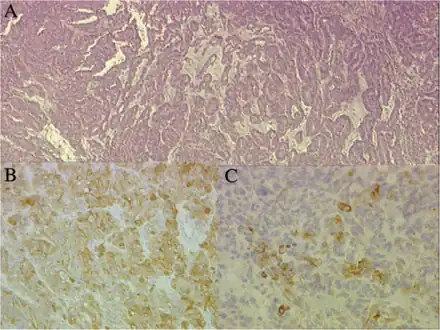

a)Papillary and tubular patterns represent the distinctive appearance of medulloepithelioma b)positivity of the neoplastic cells for S100 protein c) PanCytokeratin -

Neuronal differentiation, ranging from neuroblasts to ganglion cells, is seen in some medulloepitheliomas.